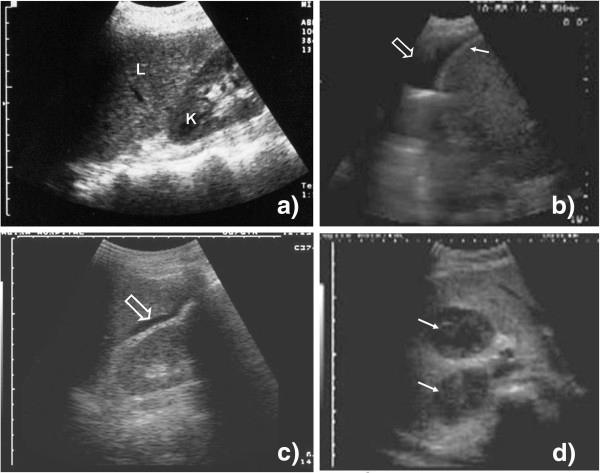

Ultrasound can rapidly identify abnormal signs, which in high prevalence settings, are highly suggestive of extra-pulmonary tuberculosis (EPTB). Unfortunately experienced sonographers are often scarce in these settings.

A protocol for focused assessment with sonography for HIV-associated tuberculosis (FASH) which can be used by physicians who are relatively inexperienced in ultrasound was developed.

The technique as well as normal and pathological findings are described and the diagnostic and possible therapeutic reasoning explained. The protocol is intended for settings where the prevalence of HIV/TB co-infected patients is high.